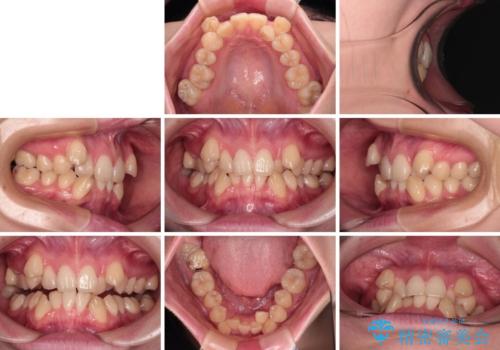

上下の八重歯とクロスバイト ワイヤー装置での抜歯矯正

- 八重歯とクロスバイトを気にして来院された患者様です。

上下ともに八重歯が顕著であり、前歯のクロスバイトがあったため、上下左右の第一小臼歯4本を抜歯し、ワイヤー装置での抜歯矯正を行うこととしました。

20歳ということもあり、歯の移動速度が非常に速く、1年強という短期間であっという間に治療を終えることができました。